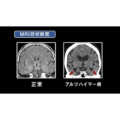

本シリーズは,医療系(医学,看護)・福祉系(福祉,介護)の学生,臨床心理士を目指す学生,また,日頃,精神領域を専門とされていないかかりつけの医師をはじめ,医療従事者,ヘルスケア産業従事者の方々に精神医学をわかりやすく解説する番組です。